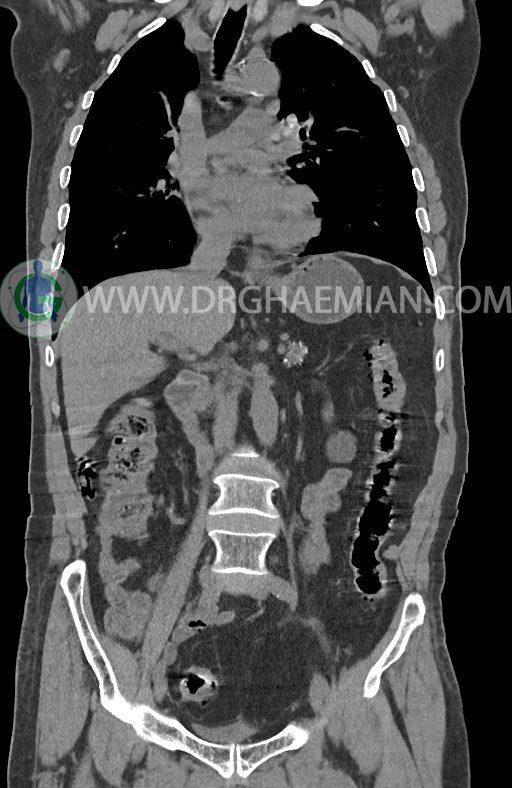

در سی تی اسکن اسپیرال ریه ها و مدیاستن، شکم و لگن با و بدون کنتراست وریدی (مولتی دیدکتور 16 با مقاطع ظریف و بازسازی کرونال) :

–توده هیپودنس به قطر 10mm در پارانشیم طحال مشهود است. Quadriphasic MRI پیشنهاد می گردد.

–آتروفی نسبی پانکراس همراه با فوکوس های کلسیفیه ی منتشر پارانشیم مطرح کننده ی پانکراتیت مزمن

-CBD بسیار دیلاته (16mm) همراه با دیلاتاسیون مجاری داخل کبدی سنترال بدون شواهد سنگ یا توده در مسیر

–کیست های کورتیکال متعدد هر دو کلیه به بزرگترین قطر 56mm

–پروستات به دیامتر عرضی بزرگ حاوی فوکوس کلسیفیه

نتیجه : T(2or3)/N2/M0